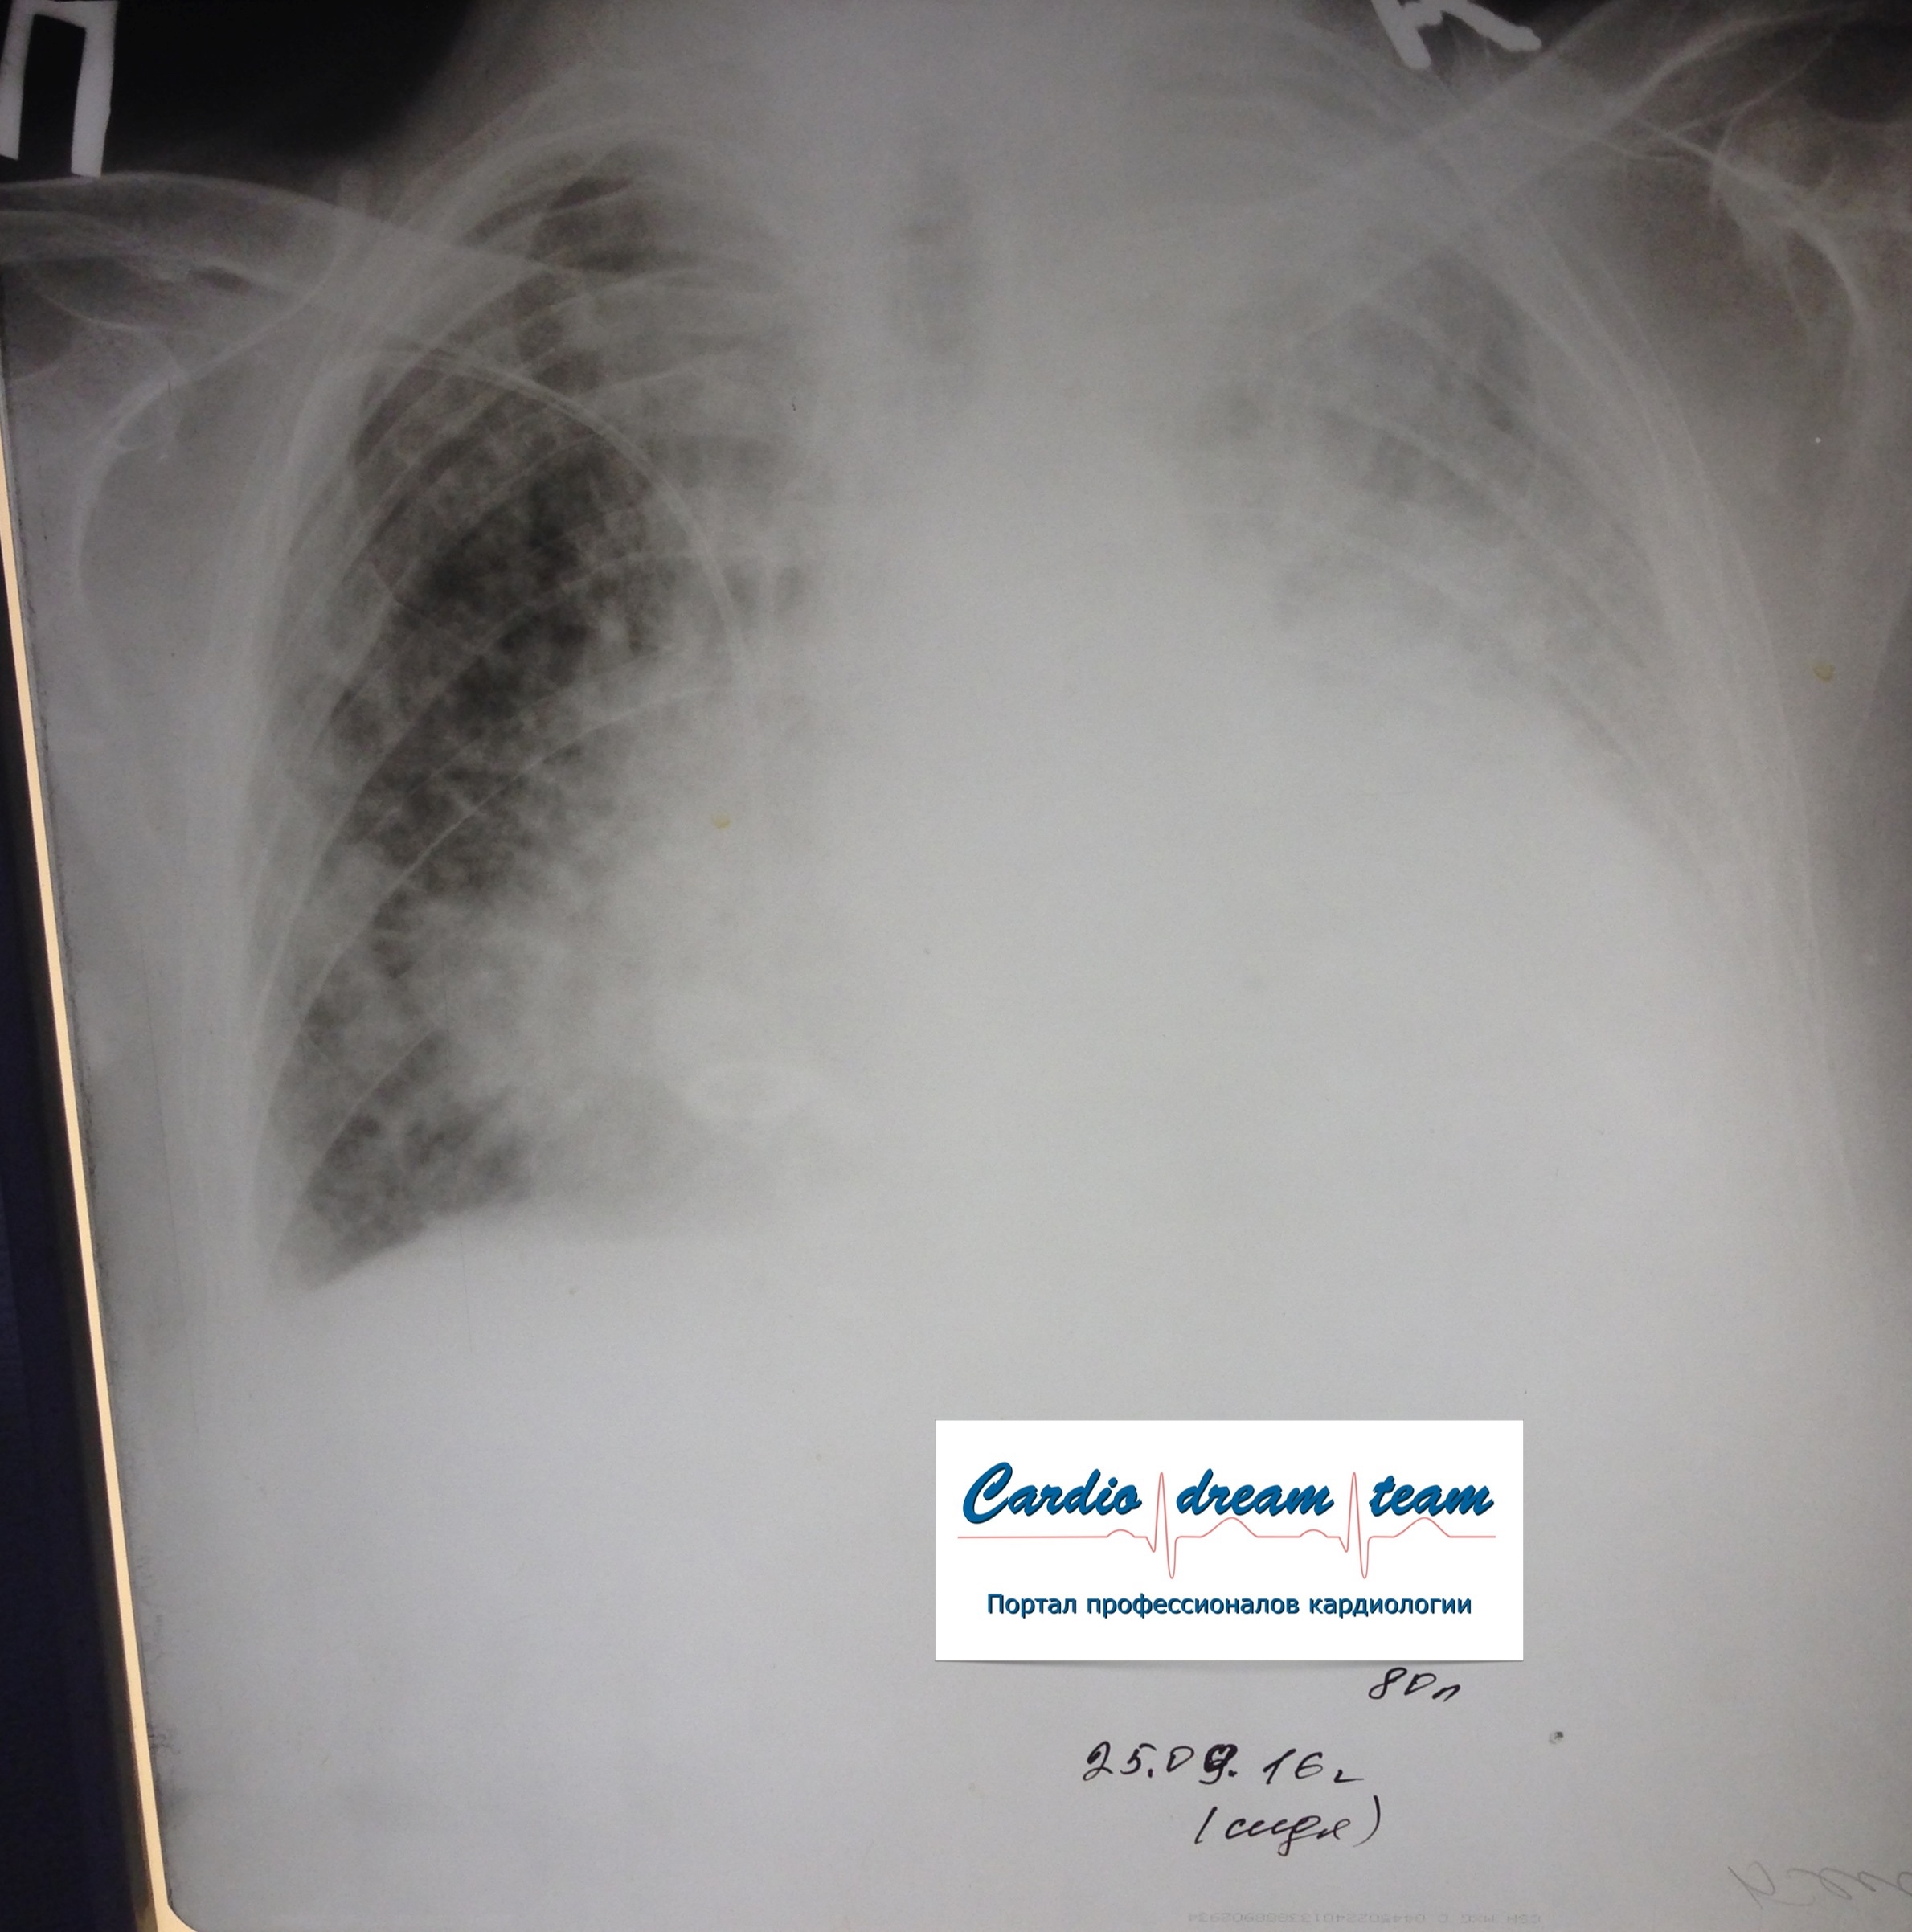

Местастазы в легкие

Обсуждалось здесь https://vk.com/club84409679?w=wall-84409679_8361%2Fall